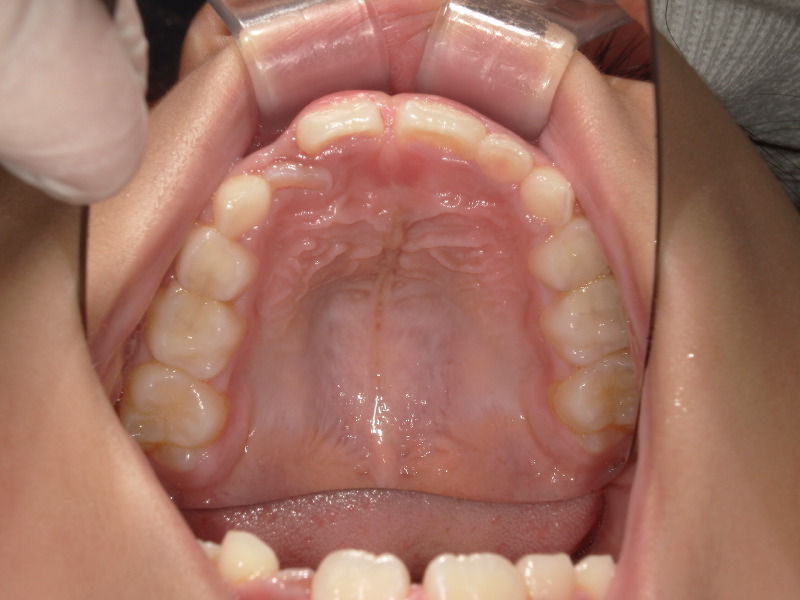

一年の上の顎の変化です。

写真左側の前から2番目の歯は大きく、今の顎のアーチの中に入れないため後ろから出ています。

右側はまだ乳歯ですが横にぴったりなので生え変わる時が経つくことが予想されていました。

ですがマウスピースとアクティビティーを進めることでしっかりと前歯の4本が横に並んでいます。

装置を外してからも順調にアクティビティーをすすめ、全ての項目が終了、マウスピースの身で続けてくれていたのですが、3番目の歯が入る頃にはここまで綺麗になっています。

しっかりと歯が綺麗なアーチに並んでいます。